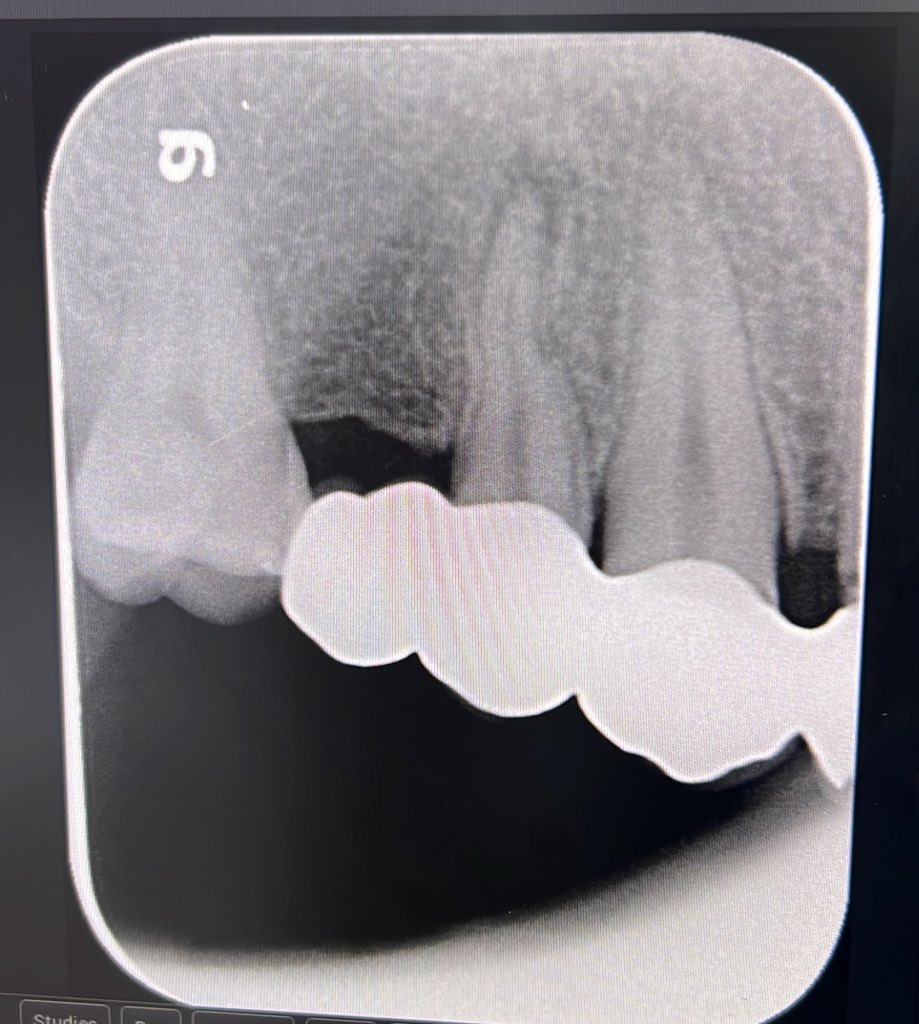

حالة جديدة اليوم ❤️

Root Canal Treatment for #36

The patient complained of severe pain,after examination we decided to do RCT.

Dx: SIP,NAP

ML wall is replaced then started RCT.

Single Cone and BC Sealer are used